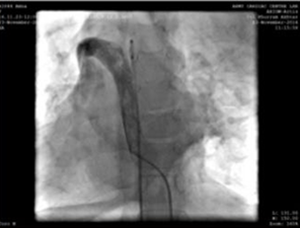

Sağ femoral ven ve arter, 5f radyal kılıf kullanıldı. Prosedür sırasında, sağ üst vena cava'ya azygous devamlılığı boyunca tahliye etmek için alt vena cava (ivc) bulduk ve daha sonra sağ atriyumdaki dilate koroner sinüsü takip ettik. Prosedürü sol iç jugular damarından (5f radyal kılıf ile erişilen) yürütme kararı alındı.

Sol jugular damarının delinmesi ve üst kol damarı-üstün vena cava-sağ atriyum bağlantı yolunu gösteren 5f anjiyografi kateteri.